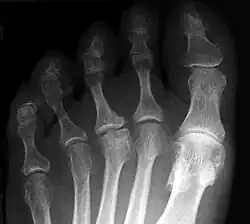

Der betroffene Vorfuß schmerzt bei Belastung, gelegentlich treten auch Schwellungen am Fußrücken im Bereich des Mittelfußköpfchens auf. Im Röntgenbild zeigen sich erst eine Veränderung in der Knochenstruktur des betroffenen Mittelfußköpfchens und erst später eine Abflachung und eine Verbreiterung (siehe Abbildung). Auf Dauer kann die Fehlform der Mittelfußköpfchens zu einer Arthrose führen.